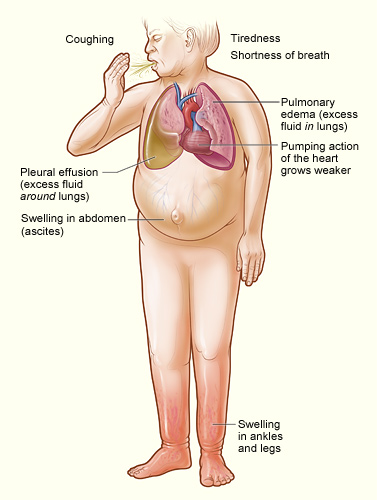

orthopnea – is dyspnea occurring lying flat. When a orthopnea patients lies flat there is an increase in venous return to the lungs that causes an increase in venous and pulmonary pressure. It stops the patient from lying normally and to sleep sitting-up. It can be commony seen in asthmatic, bronchitis, sleep apnea or heart patients.

Arthritic changes – Arthritis is related to a condition of painful joints due to inflammation or swelling. A type of arthritis is rheumatoid arthritis, it is an autoimmune disease where the immune system attacks the joints, starting with the lining of joints. Rheumatoid arthritis is heavily related to lung problems, about 80% of arthritic patients have lung-related issues, making it the second leading cause of death with rheumatoid arthritis patients. Rheumatoid arthritis caused lung problems are most commonly extra-articular i.e., outside of the joints and involves pulmonary nodules; damage to the lung airways, pleural effusion and interstitial lung disease. In rheumatoid arthritis associated interstitial lung disease the auto-immune system gets over active and attacks the lungs and causes scarring. With time, the scarring build-up leads to difficulty breathing and reduced lung function.